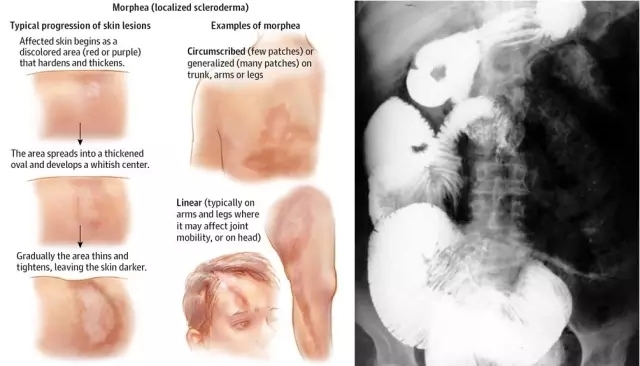

其临床特征为局限性或弥漫性皮肤增厚或纤维化,并可累及心、肺、肾、消化道等多器官的全身性自身免疫病,其病因及发病机制尚不明确。诊断依赖美国ARA分类标准(主要标准+次要标准),辅助检查方面抗核抗体、抗Scl-70抗体、抗着丝点抗体、肌电图、食管钡餐、肌肉活检等有一定的临床意义。

图为硬皮病的大体观及钡餐下可见特征性小肠膨胀

消化系统改变:食管功能障碍(90%存在,需水送服、吞咽固体食物)、食管粘膜变薄、溃疡、纤维化(可有Barrett化生)、食量下降、进食后胸骨后灼痛并饱胀反胃、吞咽困难,消化道出血,小肠区域胀痛、痉挛痛及周期性腹泻,吸收不良、严重消瘦等消化系统症状。

常见小肠运动减弱(早期神经源性,晚期肌源性损害并纤维化)、菌群紊乱、脂肪吸收障碍。肠扩张、迟缓、假性肠梗阻,积气性肠炎(偶破溃可造成气腹);腹泻便秘交替(平滑肌功能障碍致结肠蠕动减弱、直肠肛门运动障碍)。有60%左右的患者出现胰腺外分泌功能下降,胰腺坏死少见。